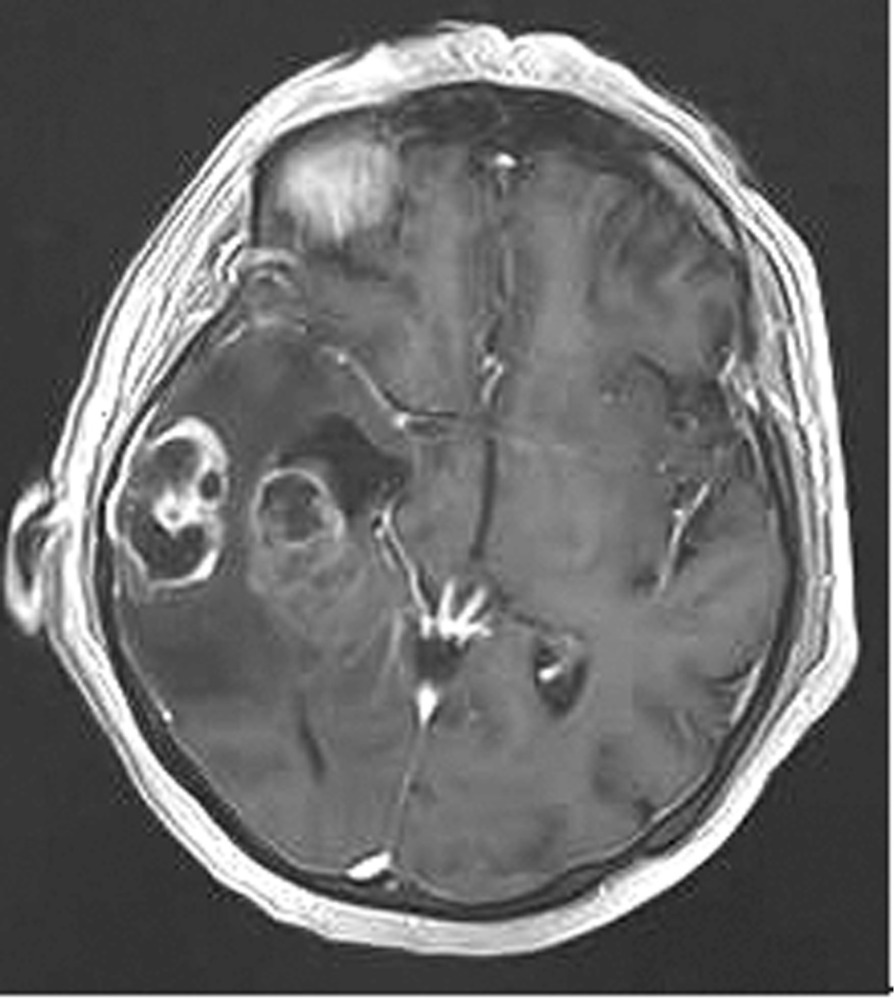

Наблюдение 1. У пациентки 70 лет за 2 мес до госпитализации появилась и стала нарастать слабость в левых конечностях, ухудшилась память на текущие события, снизилась критика собственного состояния. При магнитно-резонансной томографии (МРТ) была диагностирована внутримозговая опухоль правой височной доли с зоной перифокального отека (рис. 1).

Рис. 1. Наблюдение 1. МРТ перед операцией. Внутримозговая опухоль правой височной доли с зоной перифокального отека. Опухоль, оказавшаяся при гистологическом исследовании глиобластомой (Grade IV), удалена 02.02.16. После операции пациентка была переведена в палату пробуждения отделения реанимации, где спустя 4,5 ч (через 2 ч после экстубации) развился вторичный генерализованный судорожный приступ продолжительностью около 2 мин. Приступ был купирован внутривенным болюсным введением диазепама 10 мг и вальпроевой кислоты (конвулекс) 500 мг. Экстренное КТ-исследование выявило послеоперационные изменения правой височной доли и отсутствие хирургических осложнений (рис. 2).